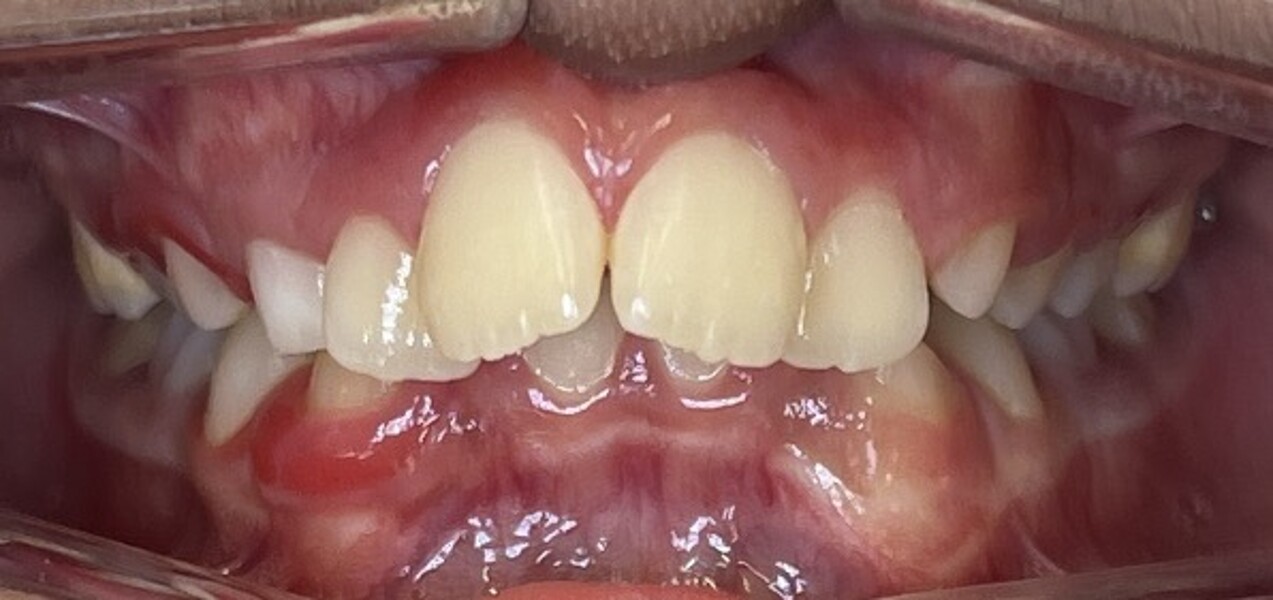

The final records demonstrated (Figs. 7–9; Table 2):

stable bilateral Class I molar and canine relationships;

normalised overjet and overbite;

well-aligned dental midlines coinciding with the facial midline;

fully developed, symmetric and parabolic dental arches; and

absence of root resorption and satisfactory root parallelism.

Radiographic evaluation showed symmetrical mandibular structures and normally seated condyles, and no pathology was detected. The findings showed correction of the skeletal Class II relationship primarily through improvement in mandibular position, as well as showed normalisation of overjet and overbite and establishment of a more balanced skeletal and dental relationship.

Figs. 8a–e: Intra-oral photographs after the second phase of treatment.